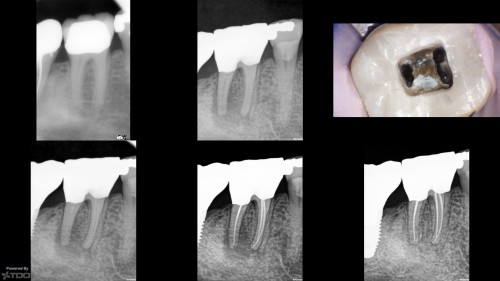

Amalgam restorations

By Viraj Vora / July 27, 2018

Recent completes: Case 1: Previously initiated, the RD could not locate negotiate/locate the canals. I […]